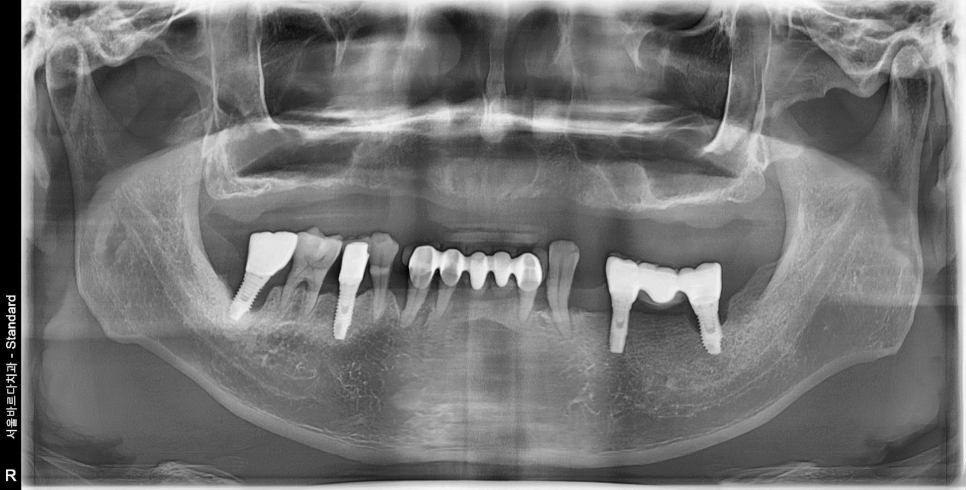

이 환자분은 위쪽 치아가 아예 없어서

총 9개의 임플란트를 심기로 계획했습니다.

양측 어금니 부분은 뼈가 얇아서

상악동 거상술과 뼈이식을 함께 진행하기로 했습니다.

식립 후 사진입니다.

231129

식립 전에는 이 하얀 부분인 뼈가 굉장히 얇았는데,

식립 후에는 이 하얀 부분이 더 많아진 것을 볼 수 있어요.

이 하얀 부분이 바로 뼈이식을 한 부위입니다.

임플란트 식립한 각도나 위치 모두 제가 원하던 위치에 심어졌습니다.